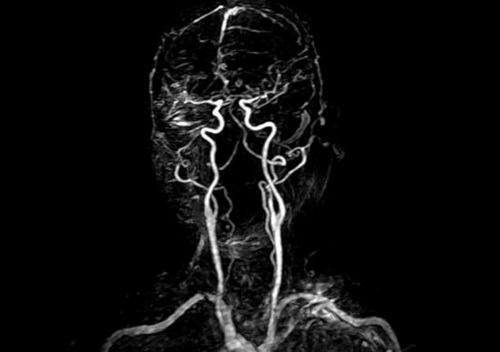

5、核磁共振成像( MRI )

在核磁共振成像仪器下,患者躺在圆柱形磁体内,暴露于强大的磁场。一旦暴露在磁场中,水分子的质子会排成一行,要是遭到无线电波的攻击,它们会立即乱作一团,不成直线。在质子重新排列过程中,电脑会收集它们的信号,并加工成图像。富含水的组织会发出更强烈的信号,在生成的图像中看上去更亮,而骨骼相对较暗。这项技术用在此处是来描述大脑和颈部动脉的。在注射了用于对比的成像剂以后,放射线专家重复扫描,这时,成像剂在血管中移动,使他们可以看清楚造成中风、脑动脉瘤和各种外伤的堵塞物。